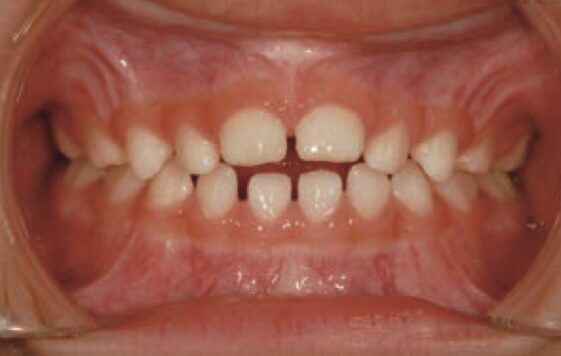

【開咬(上下の前歯の間にすき間ができる)】

指しゃぶりが続くと、上下の前歯の間にすき間ができ、前歯で噛めなくなってしまいます

公益社団法人 日本小児歯科学会 小児歯科臨床写真